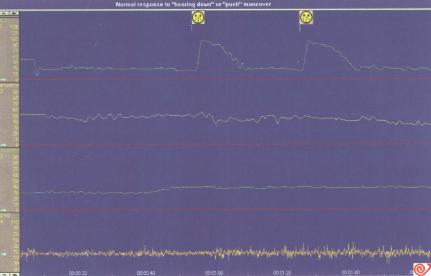

盆底痉挛综合征——肛门痉挛(图5.14)

此综合征的特征为病人用力排便时,EAS和耻骨直肠肌发生予盾性收缩,因而引起肛门功能性关闭,而不能排便。

当用力排便时,用肌电图(electromyography,EMG)可以记录到增加的EAS和耻骨直肠肌予盾性活动。

图5.14正常排便与盆底肌协调困难。用图经Williams & Wilkins允许,引自Schuster,1993。